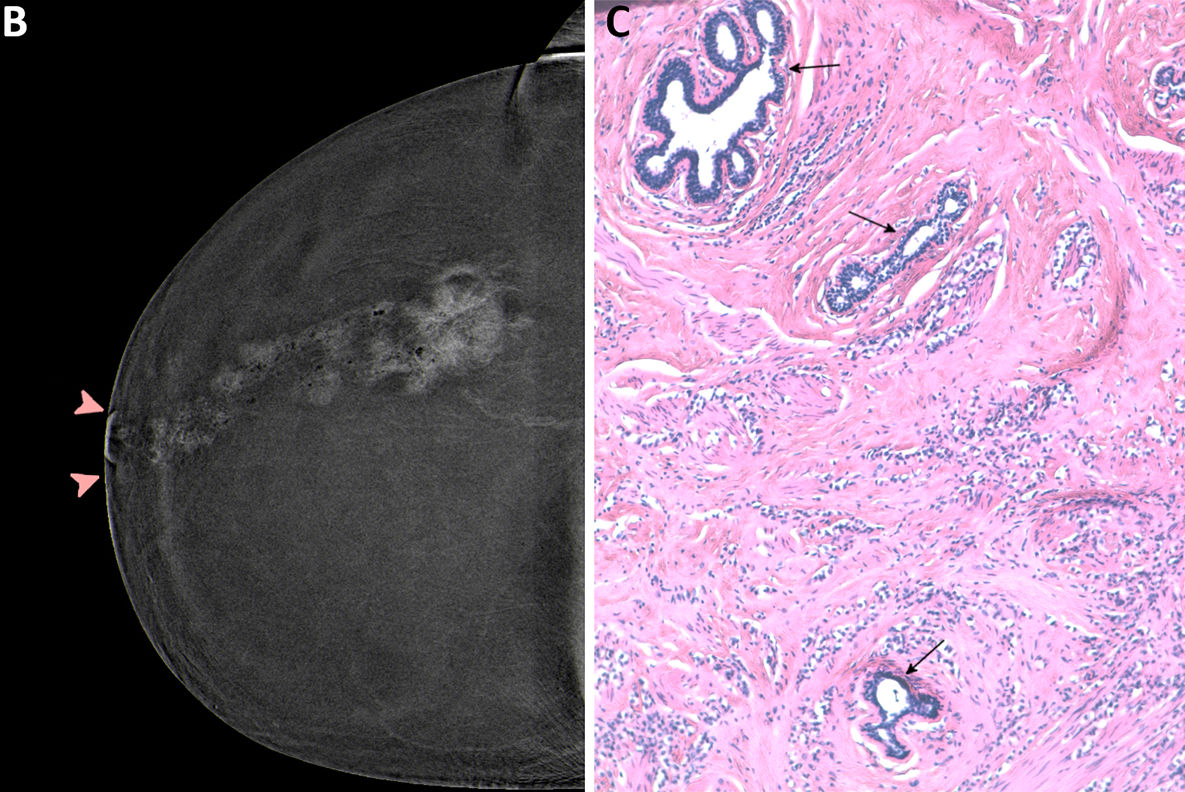

Contrast-enhanced mammography (CEM) images depict a 56-year-old woman with a history of atypical ductal hyperplasia show cancer. Images include the following: screening (A, B) mediolateral oblique views and (C, D) craniocaudal views on (A, C) low-energy images and on (B, D) recombined images in the right breast. At the central slightly outer area in the right breast, mid-depth, there is a new enhancing mass (arrows) with no correlate on low-energy images. Subsequent targeted ultrasound showed a 0.5-cm irregular hypoechoic mass (not shown) for which ultrasound-guided biopsy showed invasive carcinoma, with a 1.2-mm invasive component at surgical pathologic examination and with negative nodes. Image courtesy of the RSNA.